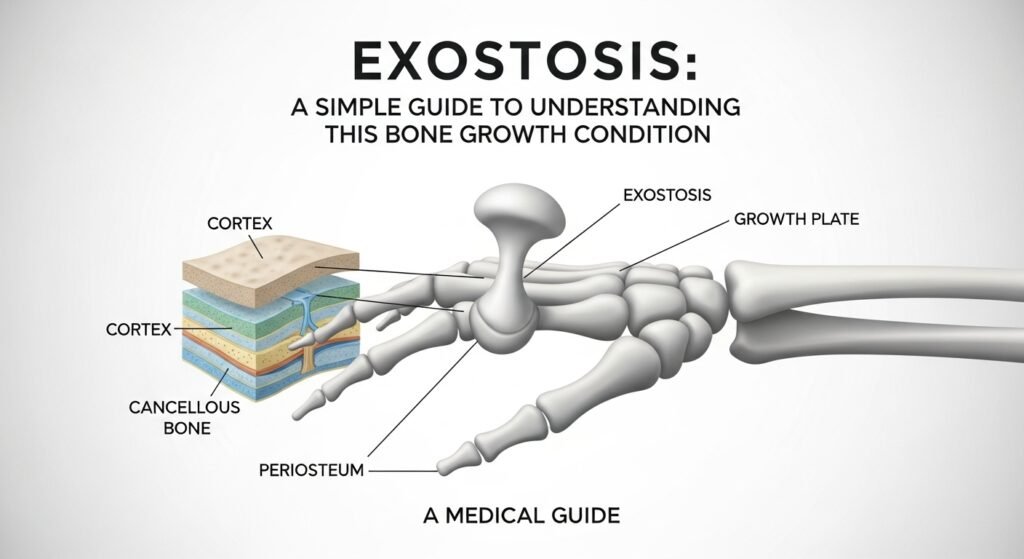

What Is Exostosis?

Exostosis refers to an abnormal growth of bone on top of a normal bone. Think of it as a little extra bump or lump made of bone tissue. These bony growths can appear on different parts of the body, like the jaw, ear canal, knee, or heel. Sometimes they grow slowly over time and go unnoticed until they start causing discomfort or begin pressing against something nearby, like muscles, skin, or nerves. While most exostoses (that’s the plural form) are non-cancerous, they should still be checked by a doctor to make sure they aren’t caused by another condition. Many people live with a small exostosis and never need treatment, though in some cases, removal is necessary.

Different Types of Exostosis

There are several types of exostosis, depending on where they appear and what causes them. One common type is osteochondroma, which usually appears near the growth plates of children and teens, often around the knee. Another type is subungual exostosis, which shows up under a toenail or fingernail and can cause pain or nail problems. Surfer’s ear, which we’ll talk more about later, is a form of exostosis in the ear canal caused by cold water exposure. There’s also buccal exostosis, found on the jawbone near the molars. Each type looks and feels different but they all have one thing in common—they’re made from bone growing in places where it typically shouldn’t.